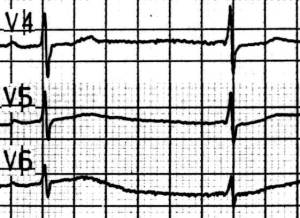

Quiz 13: AV-Block II° Wenkebach

84 jähriger Pat. als Pflegenotfall mit recidivierenden Stürzen, bekannte KHK.

Frequenz um 60/min., Linkslage, nomale Erregungsbildung, AV - Block II° Typ Mobitz 1 Wenkebach mit typischer Periodik, die PQ-Zeit nimmt von 120 msec. auf 240 msec. zu, dann fällt die Überleitung aus.